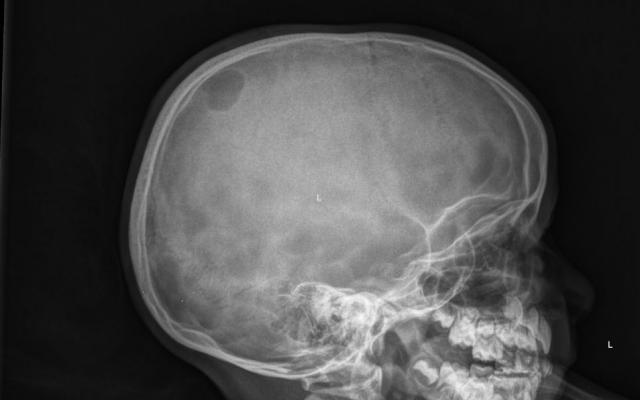

Een 6-jarig meisje van Marokkaanse afkomst kwam met haar ouders op de afdeling Spoedeisende Hulp (SEH) in verband met een zwelling op haar hoofd die mogelijk was ontstaan na een trauma. Bij neurologisch onderzoek vonden we geen afwijkingen. We spraken een wekadvies af en adviseerden een expectatief beleid. Twee weken later bracht haar vader haar nogmaals naar de SEH. Hij twijfelde over de traumatische aard van de zwelling, omdat de zwelling nog steeds niet verdwenen was. Bij lichamelijk onderzoek voelden we links pariëtaal op de schedel een niet-pijnlijke, fluctuerende zwelling met een diameter van 4 cm. De zwelling was…